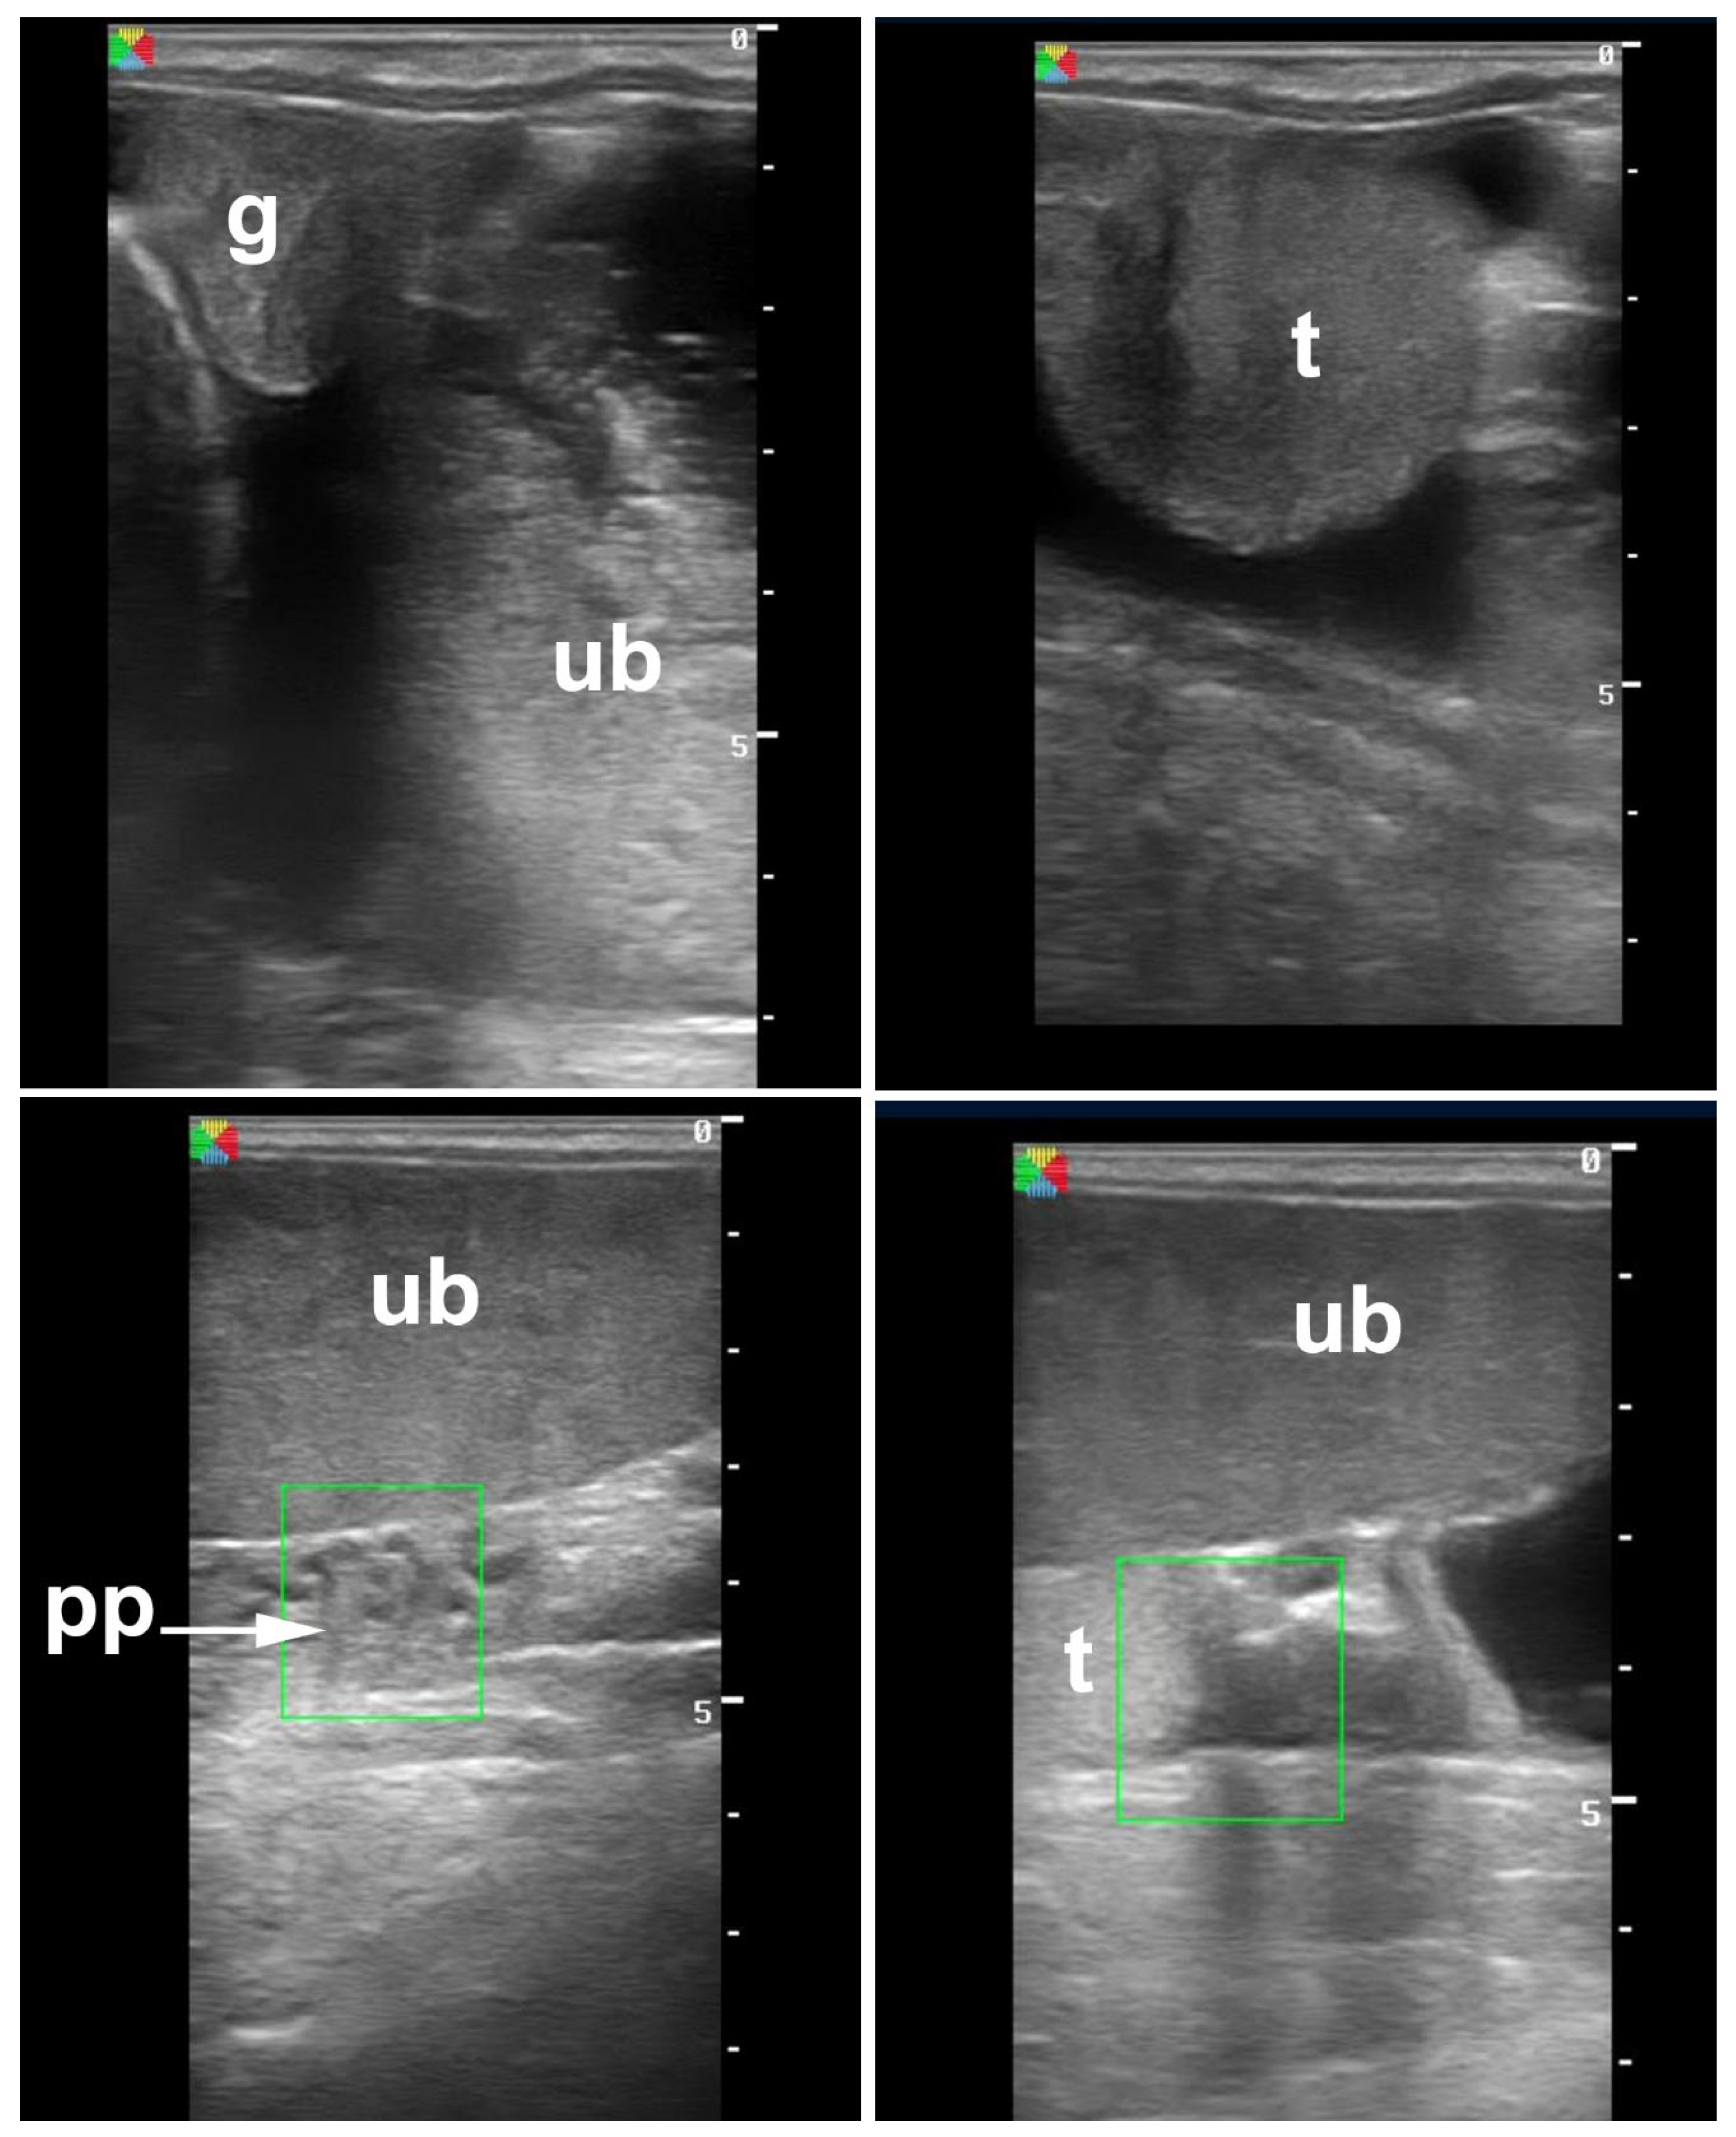

4.2. Acquired Scrotal/Inguinal Hernia

4.3. Torsion of the Spermatic Cord

4.4. Orchitis and Epididymitis

5.1. Hydrocele